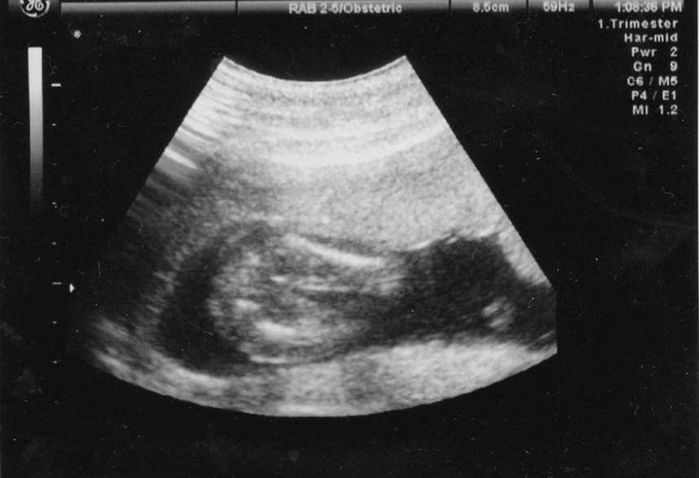

妊娠7週目のエコー写真

頭と体が2頭身に分かれました。